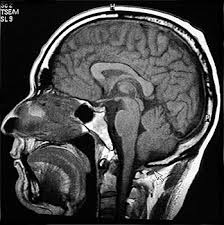

génica en células somáticas colinérgicas neuronales del cerebro anterior basal

Las células modificadas se inyectaron en el prosencéfalo con una sesión quirúrgica.

El NGF reduce la pérdida de neuronas

colinérgicas, simula la función de estas neuronas y mejora la memoria en

pacientes con de Alzheimer